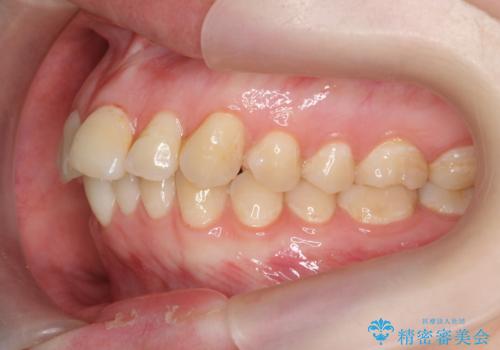

マウスピース矯正で行う出っ歯の治療

- 飛び出したように見える前歯の改善を求めて来院されました。

元々、セラミッククラウンですぐに歯並びを改善したいと希望されていましたが、目立たないマウスピース矯正治療のご提案を行なったところ矯正治療による歯並びの改善を選択されました。

矯正治療を行ったことで出っ歯の改善とともに安定した噛み合わせも手に入れることができました。